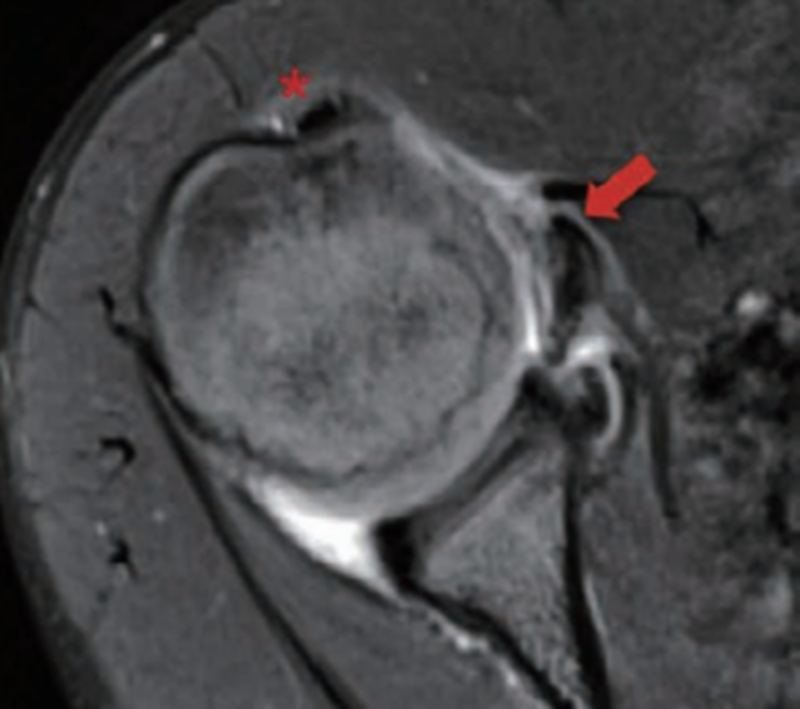

横断位MRI可以辅助判断肩胛下肌、冈下肌及小圆肌的损伤情况。在MRI上观察到肱二头肌长头腱半脱位或脱位的情况,应该高度怀疑肩胛下肌腱的部分或全层撕裂。这些病变一般在T2像上更容易分辨(图9)。

图9 MRI示肩胛下肌腱全层撕裂和肱二头肌长头腱脱位